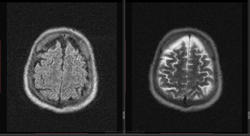

Мужчина 1964 г.р. Жалобы на нарушение памяти, снижение зрения и кратковременную потерю сознания, температура нормальная.

Я думаю что это может быть какой нибудь васкулит, либо Posterior Reversible Encephalopathy Syndrome, о чем можно думать в данном случае?

eto pres

Я представлял синдром с более выраженным изменением сигнала от белого вещества и меньшим - коры.